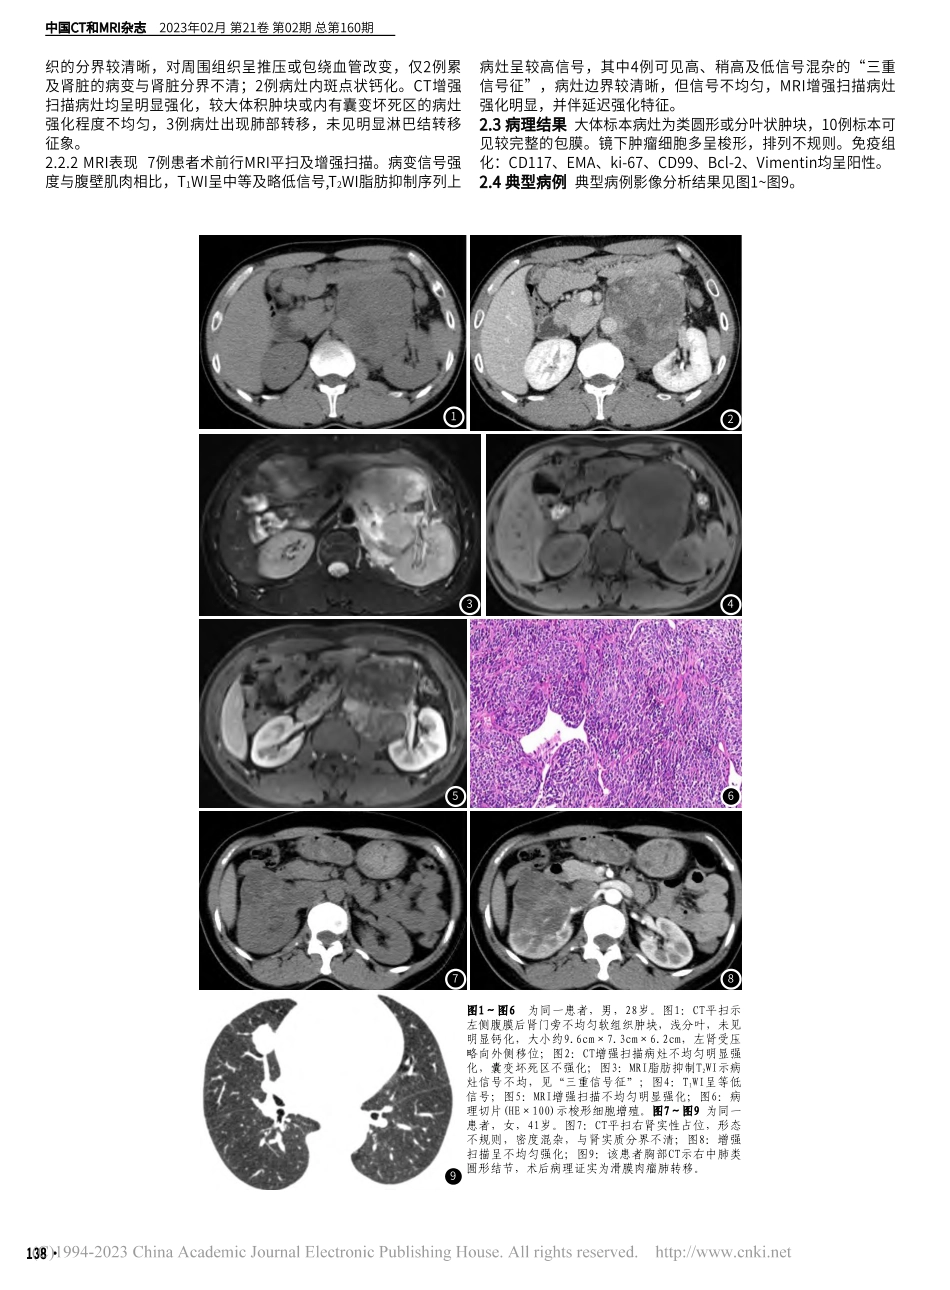

·137CHINESEJOURNALOFCTANDMRI,FEB.2023,Vol.21,No.02TotalNo.160【第一作者】皮厚山,男,副主任医师,主要研究方向:腹部及头颈部CT及MRI诊断与研究。E-mail:1720325@qq.com【通讯作者】许尚文,男,主任医师,主要研究方向:胸部及神经系统CT及MRI诊断与研究。E-mail:xu_swen@163.com论著CTandMRIofSynovialSarcomainAbdomenandPelviswithPathologicCorrelationPIHou-shan,YANGJian,CHENRui-fang,XUShang-wen*,CHENZi-qian.RadiologyDepartment,the900thHospitalofJointLogisticsSupportForce,Fuzhou350025,FujianProvince,ChinaABSTRACTObjectiveToinvestigatetheCT,MRIandclinicopathologicfeaturesofsynovialsarcoma(SS)inabdomenandpelvis.MethodsThedataof12casesofpathologicallyprovenSSwereretrospectivelyreviewed.Theirclinical,pathological,MSCTandMRIdatawassummarized.ResultsAmongthe12casesofsynovialsarcoma,9caseswerelocatedinabdomen,3casesinpelvis.Allofthetumorsweresolidsoft-tissuemasses.Thetumordiameterof8caseswaslargerthan5cm.2caseswerenearlyroundinshapeand10caseswereirregularlyshaped.Lesionswereheterogeneousindensity/signalin10cases.Inthe7patientsunderwentMRIscan,"triplesignalintensitysign"wasvisualizedin4ofthem.Alllesionswereheterogeneouslyenhanced.Remotemetastasesoccurredin3patients.ConclusionSynovialsarcomahascertaindistinctiveimagingfeatures.CTandMRIarehelpfulfordiagnosis.Keywords:SynovialSarcoma;AbdomenandPelvis;X-rayComputed;MagneticResonanceImaging滑膜肉瘤(SynovialSarcoma,SS)是一种间叶组织梭形细胞瘤,具有不同程度的上皮分化能力,临床上比较少见,据统计,恶性软组织肿瘤中SS占5%~10%[1-2]。SS是起源于间叶细胞,这种细胞有分化成滑膜组织分化的潜能,不是起源于滑膜或关节,因此可发生于任何部位,但以四肢大关节附近临床上最常见,腹盆部SS相对少见[3],术前诊断具有一定的挑战性。本文对经手术病理证实的12例腹盆部滑膜肉瘤的CT及MRI影像、病理及临床资料进行回顾性分析,以提高术前诊断水平。1资料与方法1.1一般资料选取联勤保障部队第九〇〇医院2014年6月至2020年6月12例腹盆部滑膜肉瘤患者,男性7例,女性5例,年龄17~65岁,中位37岁。所有患者术前接受了CT或/和MRI检查,患者术后标本经普通病理和病理免疫组化分析,均诊断滑膜肉瘤。搜集的临床...